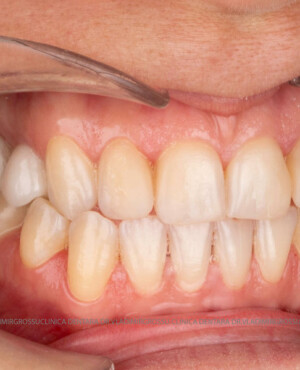

Cazuri clinice

Caz 2

Restaurări cu coroane din zirconiu vs fațete ceramice

Atât fațetele ceramice (Emax sau 360) cât și coroanele din zirconiu sunt soluții estetice eficiente. Fațetele sunt indicate pacienților cu o poziție dentară relativ uniformă și dinți vitali, deoarece implică șlefuirea minimală a smalțului (0,4–0,7 mm) și fixarea adezivă sub coferdam. În cazurile cu dinți tratați endodontic, coroane pigmentate, proteze pe implanturi sau când este necesară o creștere semnificativă a ocluziei, se preferă coroanele din zirconiu.